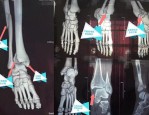

欧洲杯期间崴脚致小腿骨折,足球迷就医需谨慎

极目新闻记者 赵雪纯 通讯员 王竹君 阮晓芳 欧洲杯不仅“点燃”了球迷的心,也让更多人奔向绿茵场一展身手。原本有伤在脚的向先生(化姓)按捺不住内心的激动,趁欧洲杯比...

-